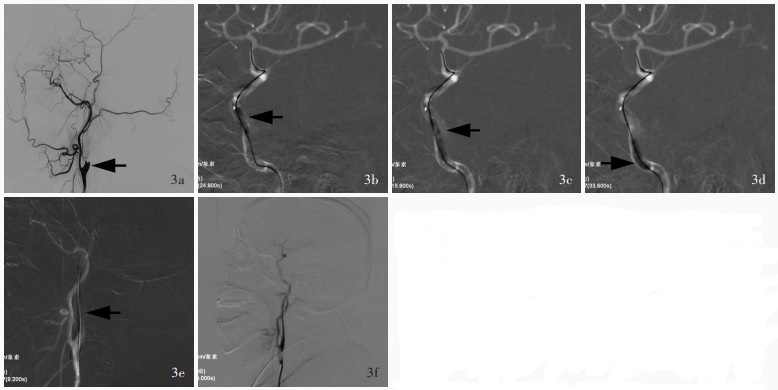

Zhao TY , Xu GQ , Xue JY , Bai WX , Cai DY , Yang BW , Shi WY , Li TX , Gao BL . Significance of atherosclerotic plaque location in recanalizing non-acute long-segment occlusion of the internal carotid artery. Sci Rep, 2024, 14: 10945.

|